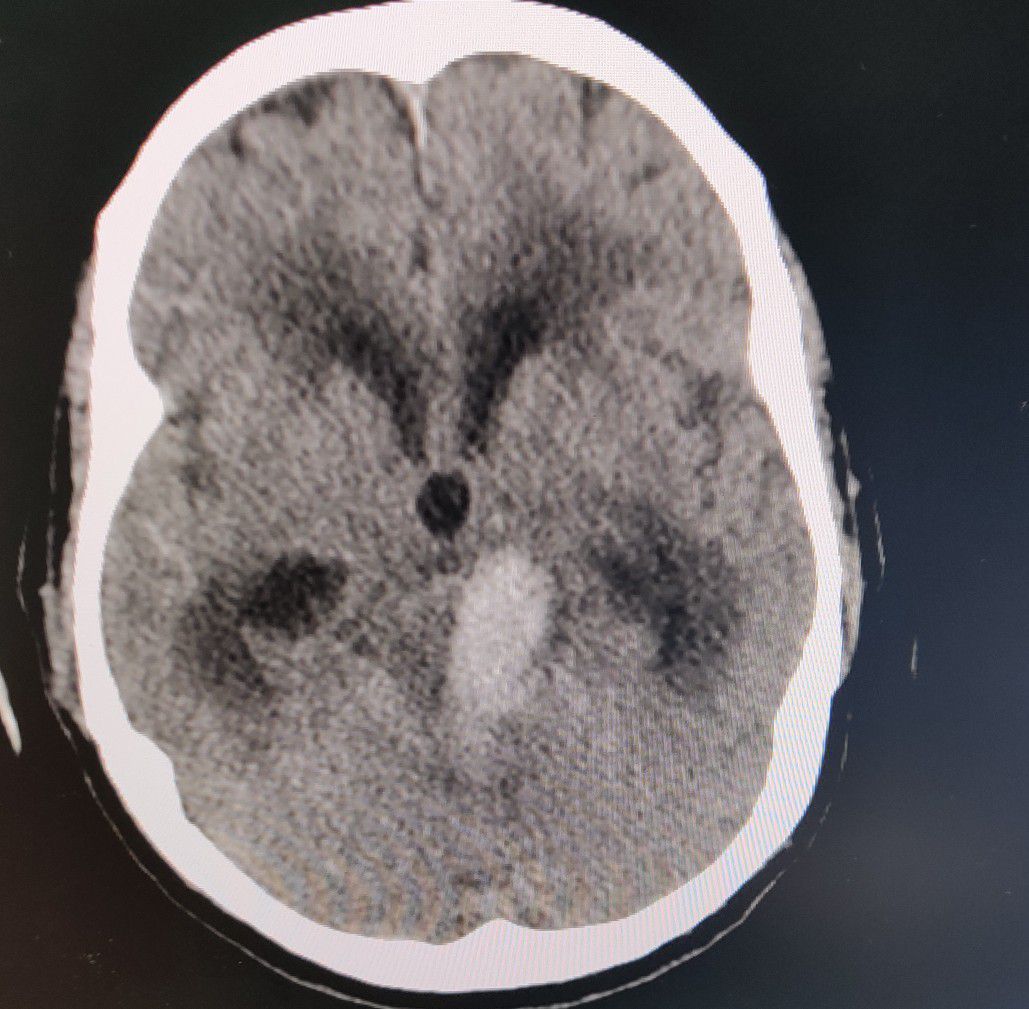

Hemorrhagic CVA

Cva

Hemorrhagic